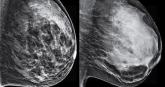

In which categories of breast density ( FIGURE 1 ) does tomosynthesis/3D mammography increase cancer...